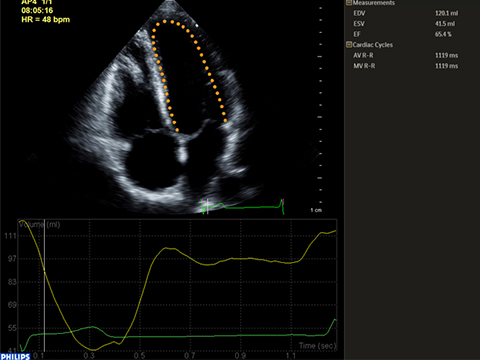

HeartModelᴬ⋅ᴵ⋅は、最上位の優れた新しいAnatomically Intelligent Ultrasound(AIUS)アプリケーションで、1つのLive 3Dボリュームから左室(LV)および左房(LA)のボリュームと駆出率を自動的に検出、セグメント化、定量化します。HeartModelᴬ⋅ᴵ⋅は日々の心エコー検査において最新の自動定量化、3D表示、確実な再現性、および最大82%の時間短縮を実現します。

本研究では、2DとLive 3D HeartModel間の定量化を比較し、HeartModelで自動機能を使用した場合には82%の時間短縮、若干の編集が必要な場合でも63%の時間短縮が実証されました。

より多くのユーザーが再現性の向上により、従来の方法より短時間、少ないステップで診断の信頼性を高めることができます。